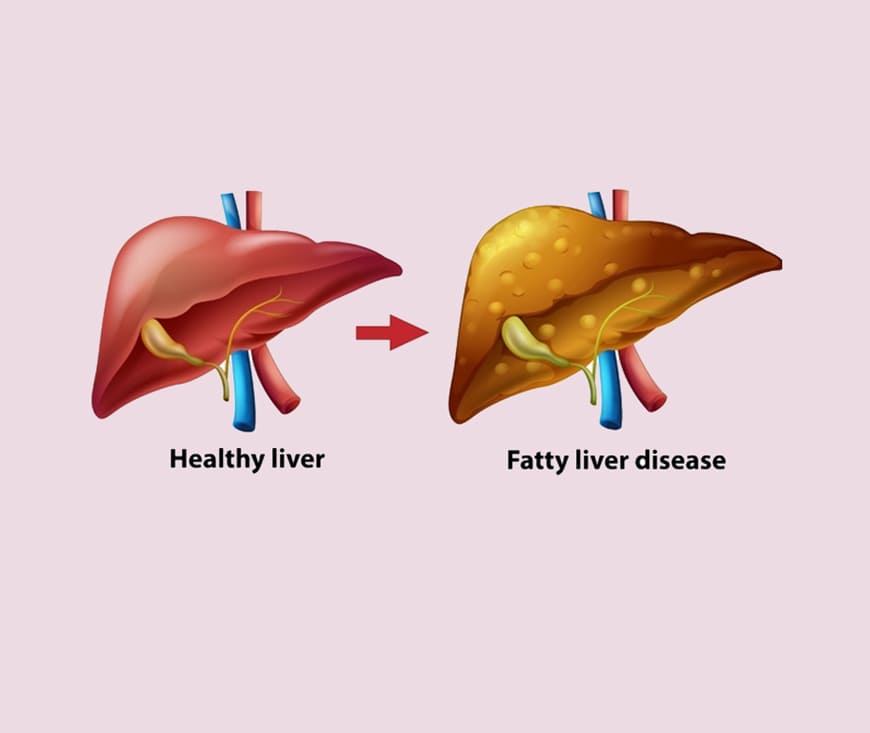

Fatty liver disease treatment focuses on lifestyle changes and managing underlying conditions. A balanced diet, regular exercise, and weight loss are essential in reducing liver fat. Medications may be prescribed for related conditions like diabetes or high cholesterol. Early diagnosis, along with regular monitoring, can prevent complications. Always consult a healthcare provider for personalized treatment.